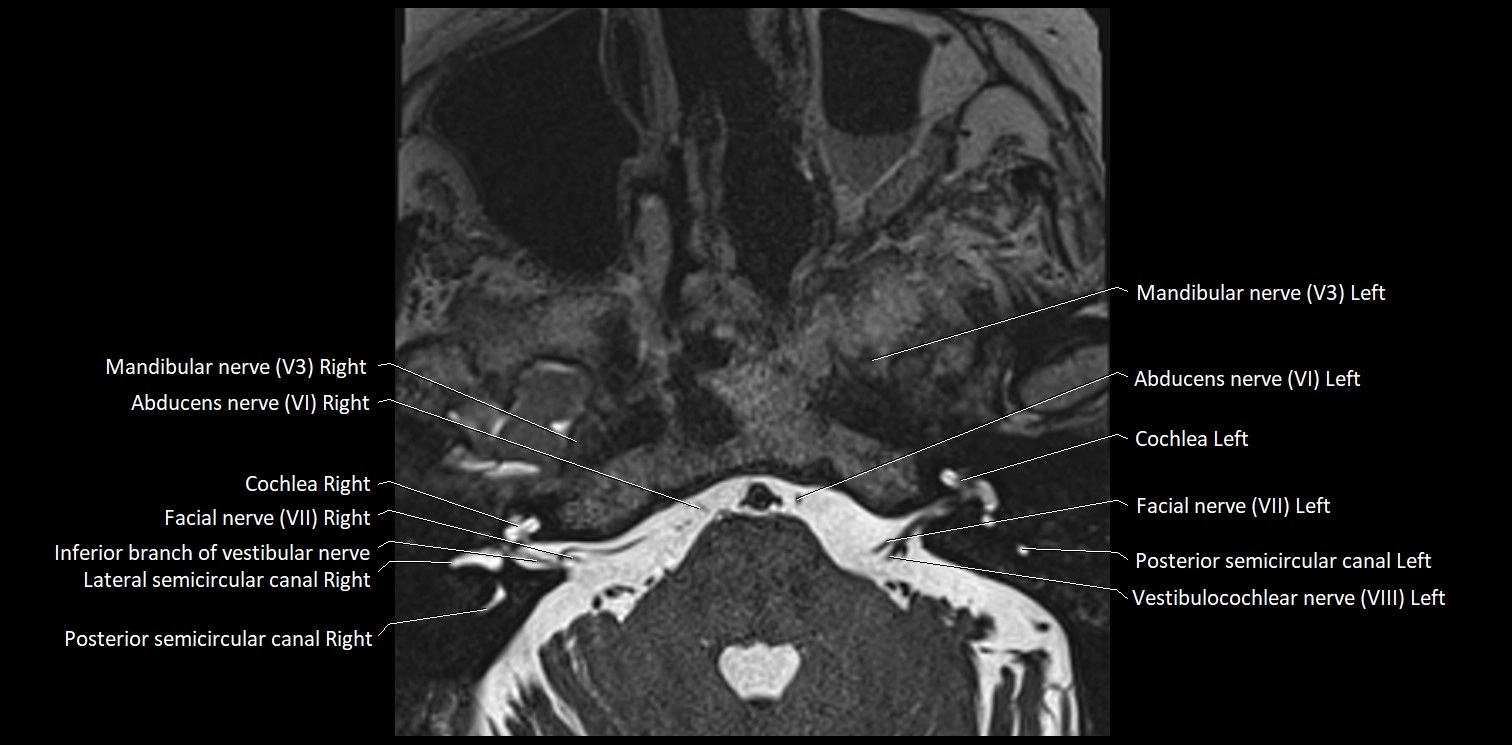

MRI Appearance

• The abducens nerve is a small, thin, linear structure

• Best visualized on high-resolution T2-weighted 3D MRI sequences (e.g., FIESTA or CISS)

• Seen as a hypointense (dark) line running from the brainstem at the pontomedullary junction, traversing the prepontine cistern, and entering Dorello’s canal under the petrosphenoidal ligament, then into the cavernous sinus, and finally the orbit

• May be challenging to visualize in standard MRI due to its small size

• Pathology may be inferred by absence, displacement, or enhancement of the nerve

MRI images

image